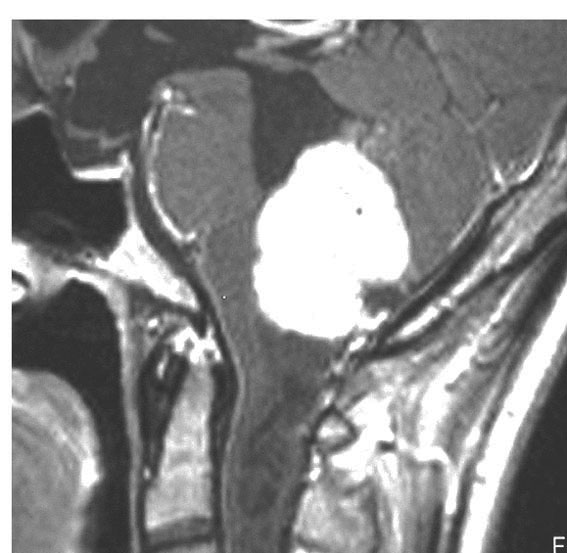

第4脳室腫瘍のMRI像

左は脳幹部腫瘍(退形成性神経節膠腫),右は小脳腫瘍(毛様細胞性星細胞腫)です。どちらも第4脳室を埋め尽くすように発育しています。これらはどちら側から発生したかが明瞭な例ですが,第4脳室腫瘍の中には脳幹部からか小脳からか解らないものもあります。でも多くは小脳側からです。脳幹部側からで注意しなければならないのは上衣腫と血管芽腫です。